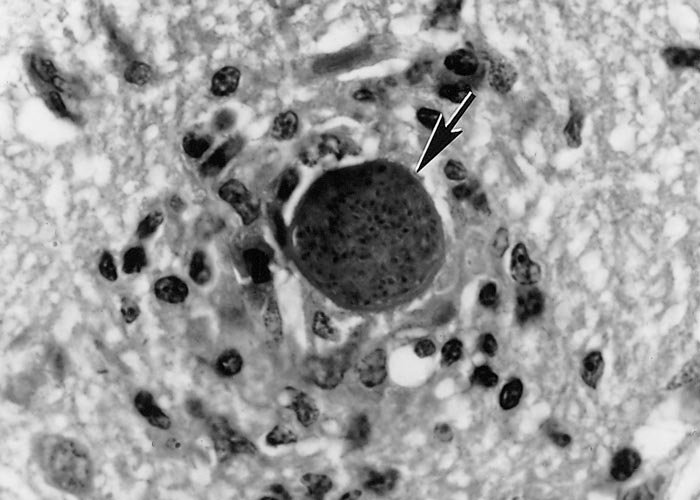

Tissue cysts are often round to oval in shape (Figure 4). Most tissue cysts studied were from the brain and spinal cord, the majority from naturally infected dogs. Tissue cysts in the brain are round to oval and up to 107 µm in diameter. The cyst wall is 0.5 to 4.0 µm thick, both in live, unstained preparations and in histological sections.51 The cysts in myocytes are elongated and may be up to 100 µm long, and have a thin cyst wall.71, 141 Histologically tissue cysts are rare in other organs or tissues of naturally infected animals. The tissue cyst wall is smooth and up to 4 µm thick, presumably depending on the duration of the infection. Septa are absent in the cysts and there is no secondary cyst wall (Figure 5). The tissue cyst wall is elastic, argyrophilic, has a wavy contour, and stains negative with Periodic-acid Schiff (PAS). Bradyzoites are slender and contain the same organelles as tachyzoites except that there are fewer rhoptries and more PAS-positive (amylopectin) granules in the bradyzoites. Tissue cysts may degenerate and cause an inflammatory reaction by the host (Figure 6).

Figure 4 Tissue cysts (arrows) of Neospora caninum

- Section of a calf brain. Note small tissue cyst with thin cyst wall. Haematoxylin and eosin stain

- Intraneuronal tissue cyst in a section of the spinal cord of a calf. Haematoxylin and eosin stain

- Intraneuronal tissue cyst in a section of spinal cord of a calf. Note silver-positive cyst wall. Silver stain

- Tissue cyst in a brain squash of an experimentally infected mouse. Note thick cyst wall (opposing arrowheads). Unstained